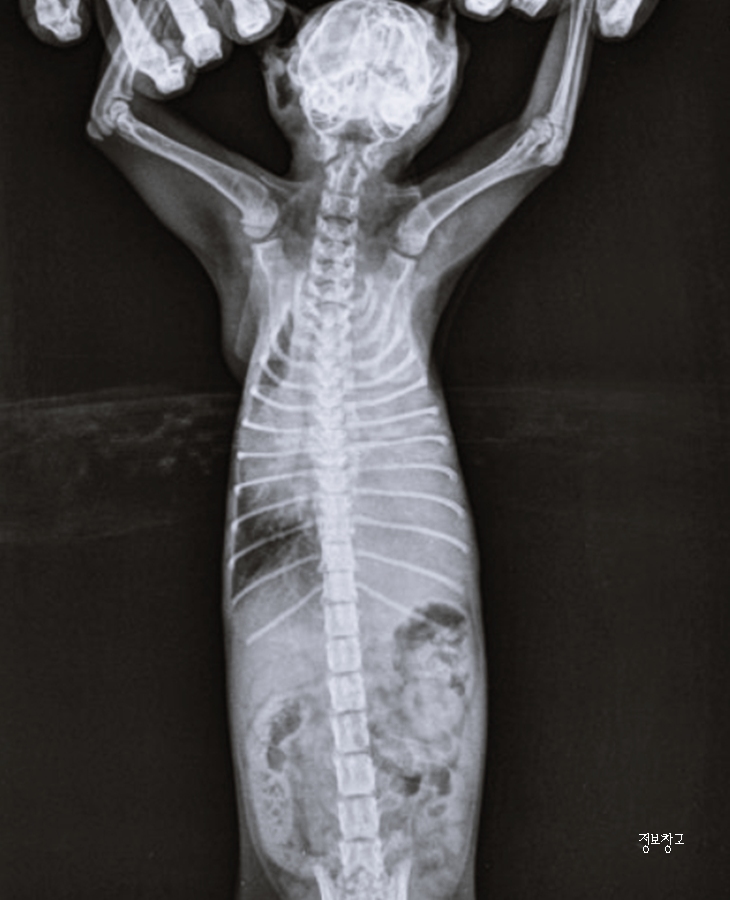

✔ 흉수 (흉강에 물이 차는 경우)

흉수는 호흡을 어렵게 만드는

응급 상황이 될 수 있습니다.

대표 증상

- 빠른 호흡

- 힘들어 보이는 호흡

- 활동 감소